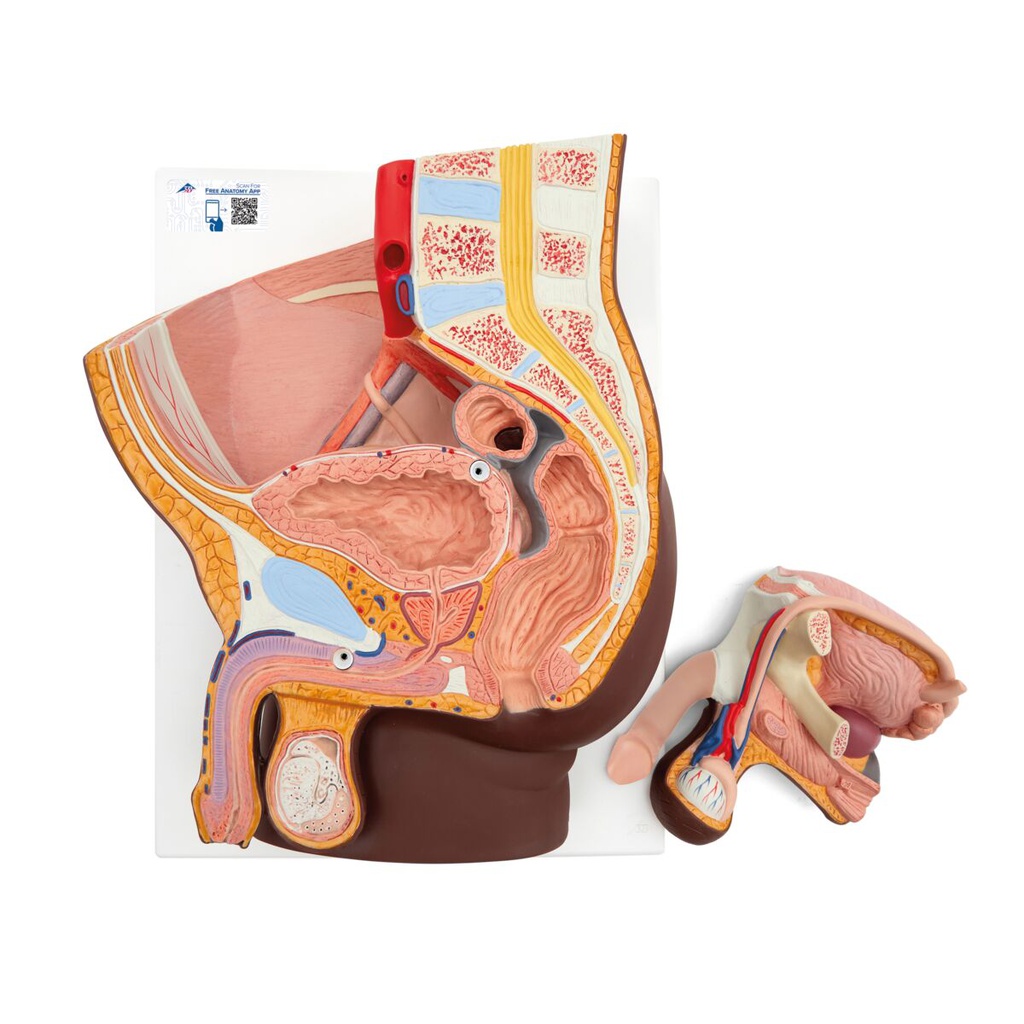

Male pelvis model in median section, 2 part

The male pelvis anatomy model is shown in median section. One half of male genital organs with bladder is shown at the normal position in the male pelvis. The rectum is removable for a more detailed study of the male pelvic anatomy. This high quality anatomy model is delivered on baseboard offering the possibility to be mounted to the wall.